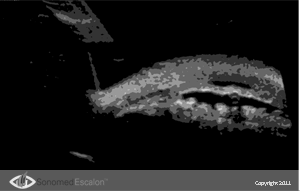

?сследование при помощи VuMAX® функций проходимости в случаях трабекулэктомии и конъюнктивальном химозе, можно оценить успешность и эффективность проведенных пост-оперативных вмешательств таких, как фильтрующая хирургия. Кроме того, VuMAX® обеспечивает четкую визуализацию Шлеммова канала, что необходимо в случаях проведения вискоканалостомии.